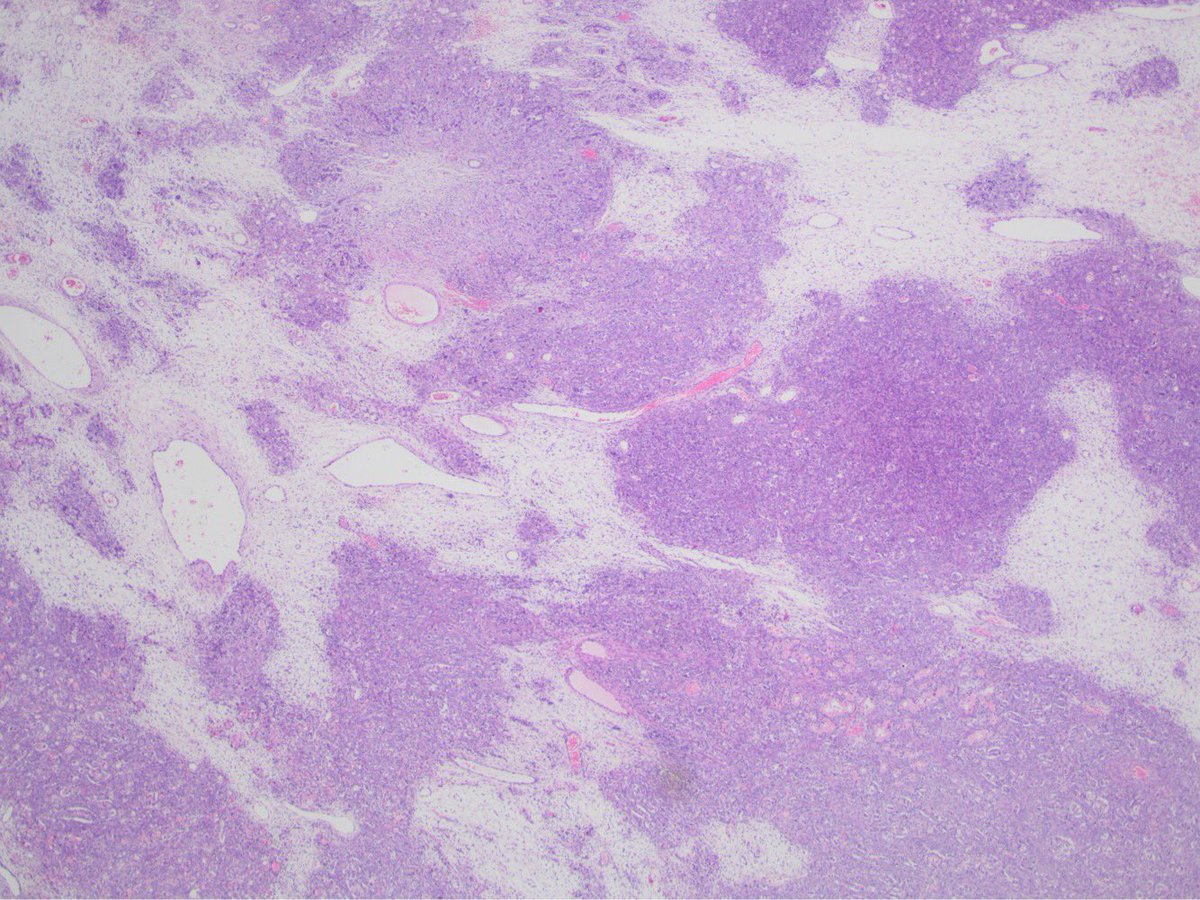

We're sharing 2 cases today since we missed #GYNPath Day 5 last week. What’s your #DailyDx of this uterine mass? We’ll tweet the answer and some quick facts tomorrow! #UMichPath

What’s your #DailyDx of this uterine mass?

We’ll tweet the answer and some quick facts tomorrow! #UMichPath

A: Lipoleiomyoma. A variant of uterine leiomyomata. Gross: Well circumscribed mass with alternating yellow and white areas. Histo: Variable admixture of bland smooth muscle cells and adipocytes. Very rarely can have glandular elements (adenolipoleiomyoma). #GYNPath #DailyDx

UMichPath's tweet image. A: Lipoleiomyoma. A variant of uterine leiomyomata.  Gross: Well circumscribed mass with alternating yellow and white areas. Histo: Variable admixture of bland smooth muscle cells and adipocytes. Very rarely can have glandular elements (adenolipoleiomyoma). #GYNPath #DailyDx